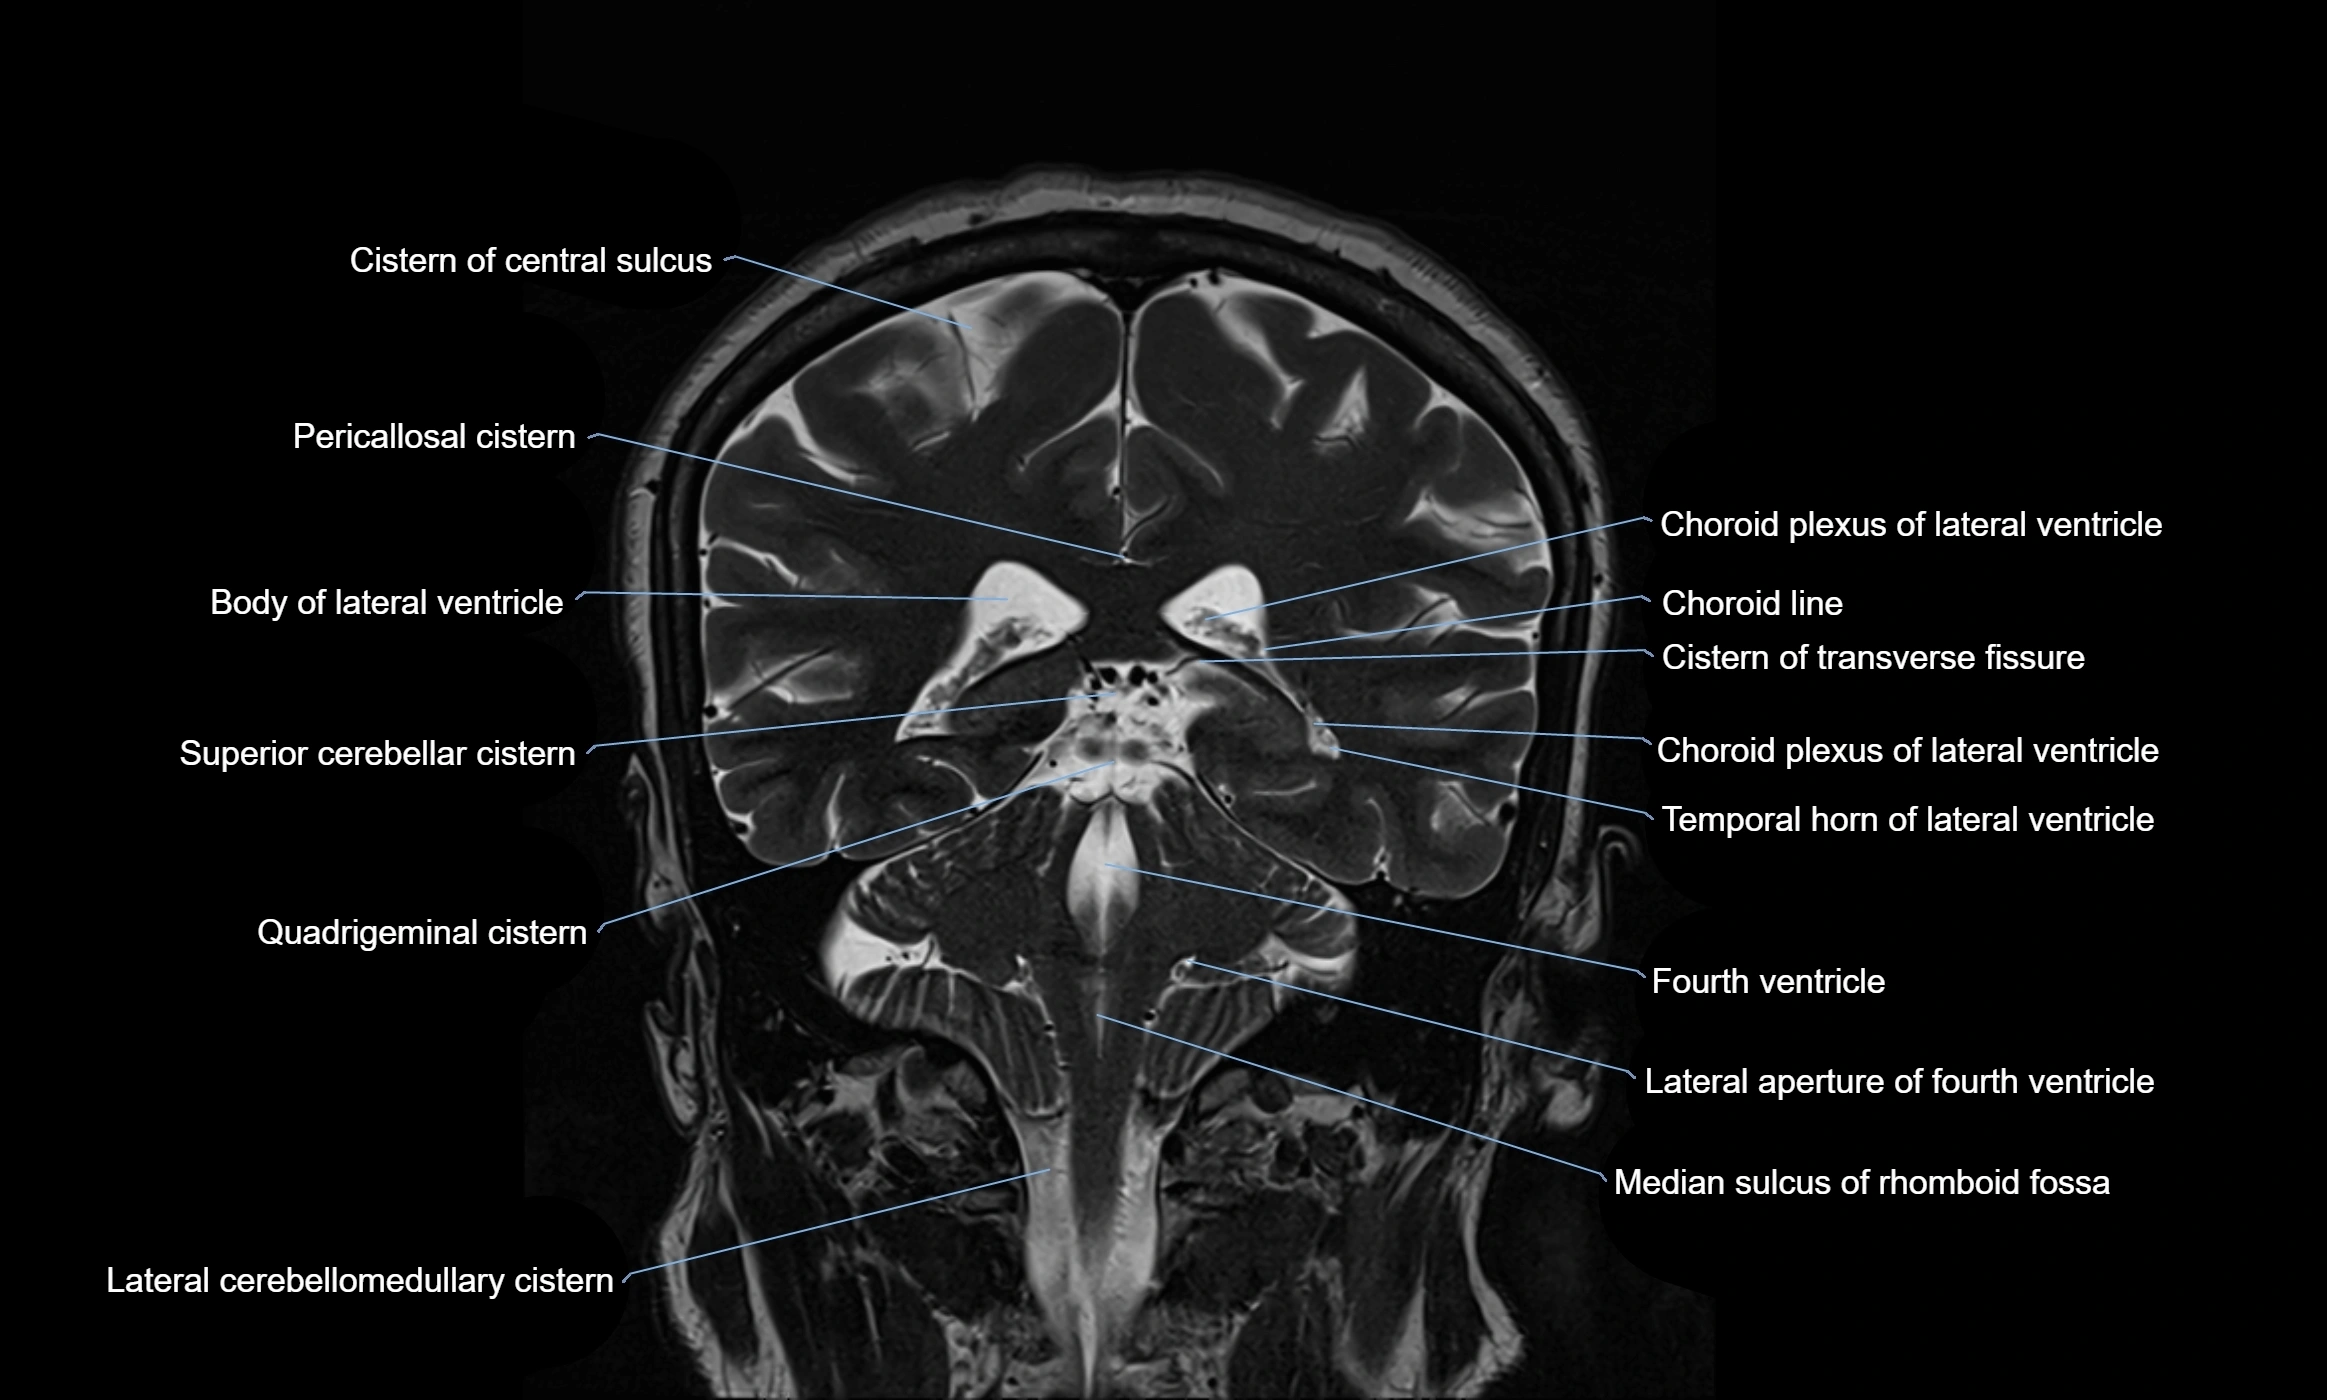

MRI images

image